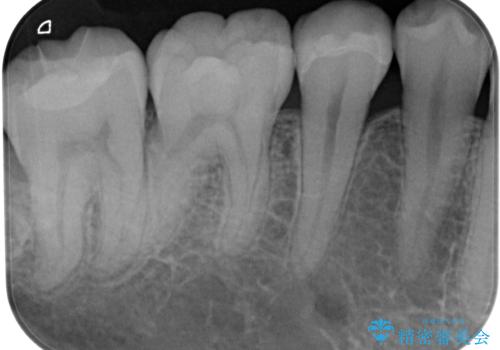

- 銀歯やむし歯でものが挟まるところが気になるとのことで来院された患者様です。

左上の奥歯は神経が失活しており、根管治療が必要な状態でした。

その他は銀歯のインレー(部分的な詰め物)が装着されており、それらはむし歯を除去した後にセラミックインレーにて修復治療を行い、左下と根管治療を行う左上の奥歯はオールセラミッククラウンにて補綴治療を行うこととしました。